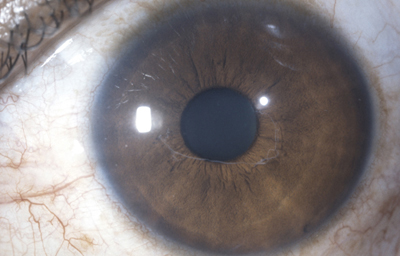

Aniridia completa, catarata y distrofia corneal de la aniridia

Archivo Dr. Francisco Barraquer

Caso de paciente con Coloboma en un ojo y Aniridia en el contralateral

OD

Archivo Fotográfico Dr. Francisco Barraquer

OI

Archivo Dr. Francisco Barraquer